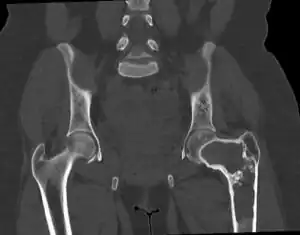

| Fibrous dysplasia of the top of thigh bone at the hip | |

On x-ray, fibrous dysplasia appears as bubbly lytic lesions, or a ground glass appearance. Computerized tomography (CT) or magnetic resonance imaging (MRI) scans may be used to determine how extensively bones are affected. CT can better demonstrate the typical "ground glass" appearance, which is a highly specific radiological finding, while MRI can show cystic areas with fluid contents.[18] A bone scan uses radioactive tracers, which are injected into the bloodstream. The damaged parts of bones take up more of the tracer, which show up more brightly on the scan. A biopsy, which uses a hollow needle to remove a small piece of the affected bone for laboratory analysis, can diagnose fibrous dysplasia definitely.